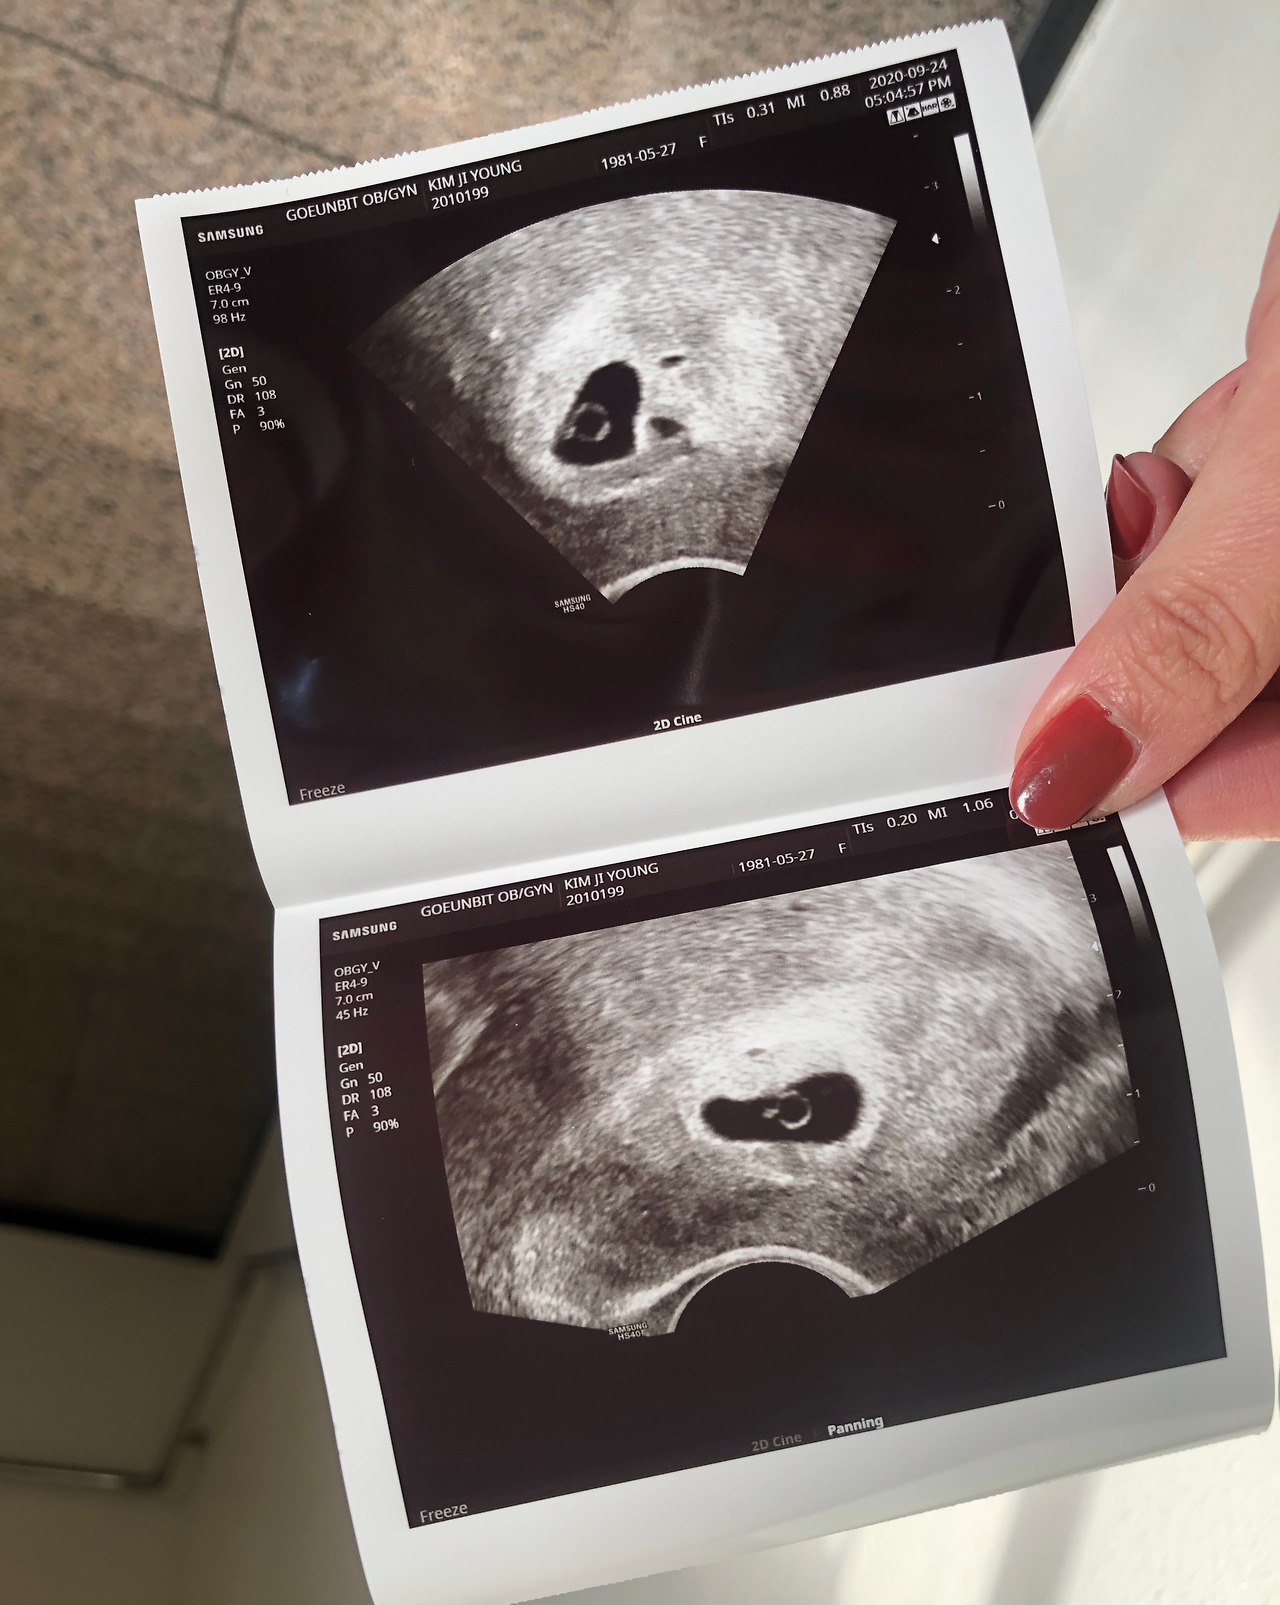

이런 그가 내 남편, 내 아이의 아빠라면 뭐가 됐든 두렵지 않을 것 같다는 확신이 쌓였다. 처음 병원을 다녀오는 날, 작지만 다이아몬드처럼 곱게 빛나는 생명 앞에 한동안 아무 말도 할 수 없었다. 지키고 싶다는 욕심과 지켜야 한다는 책임감에 마음을 졸일 게 뻔하지만, 이렇게 기적처럼 찾아온 생명이니 잘 버텨주리라 믿으며 기꺼이 걱정 많은 겁쟁이가 되어 보기로 마음먹었다. 그렇게 임신 중기로 접어들었고, 빛 바랜 걱정과는 다르게 반짝반짝 빛나는 내 딸을 위해 브런치에 글을 연재해 보기로 했다.

2020년 9월 23일 5주 1일 첫 병원 방문한 날